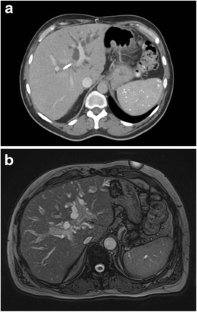

Fig. 2